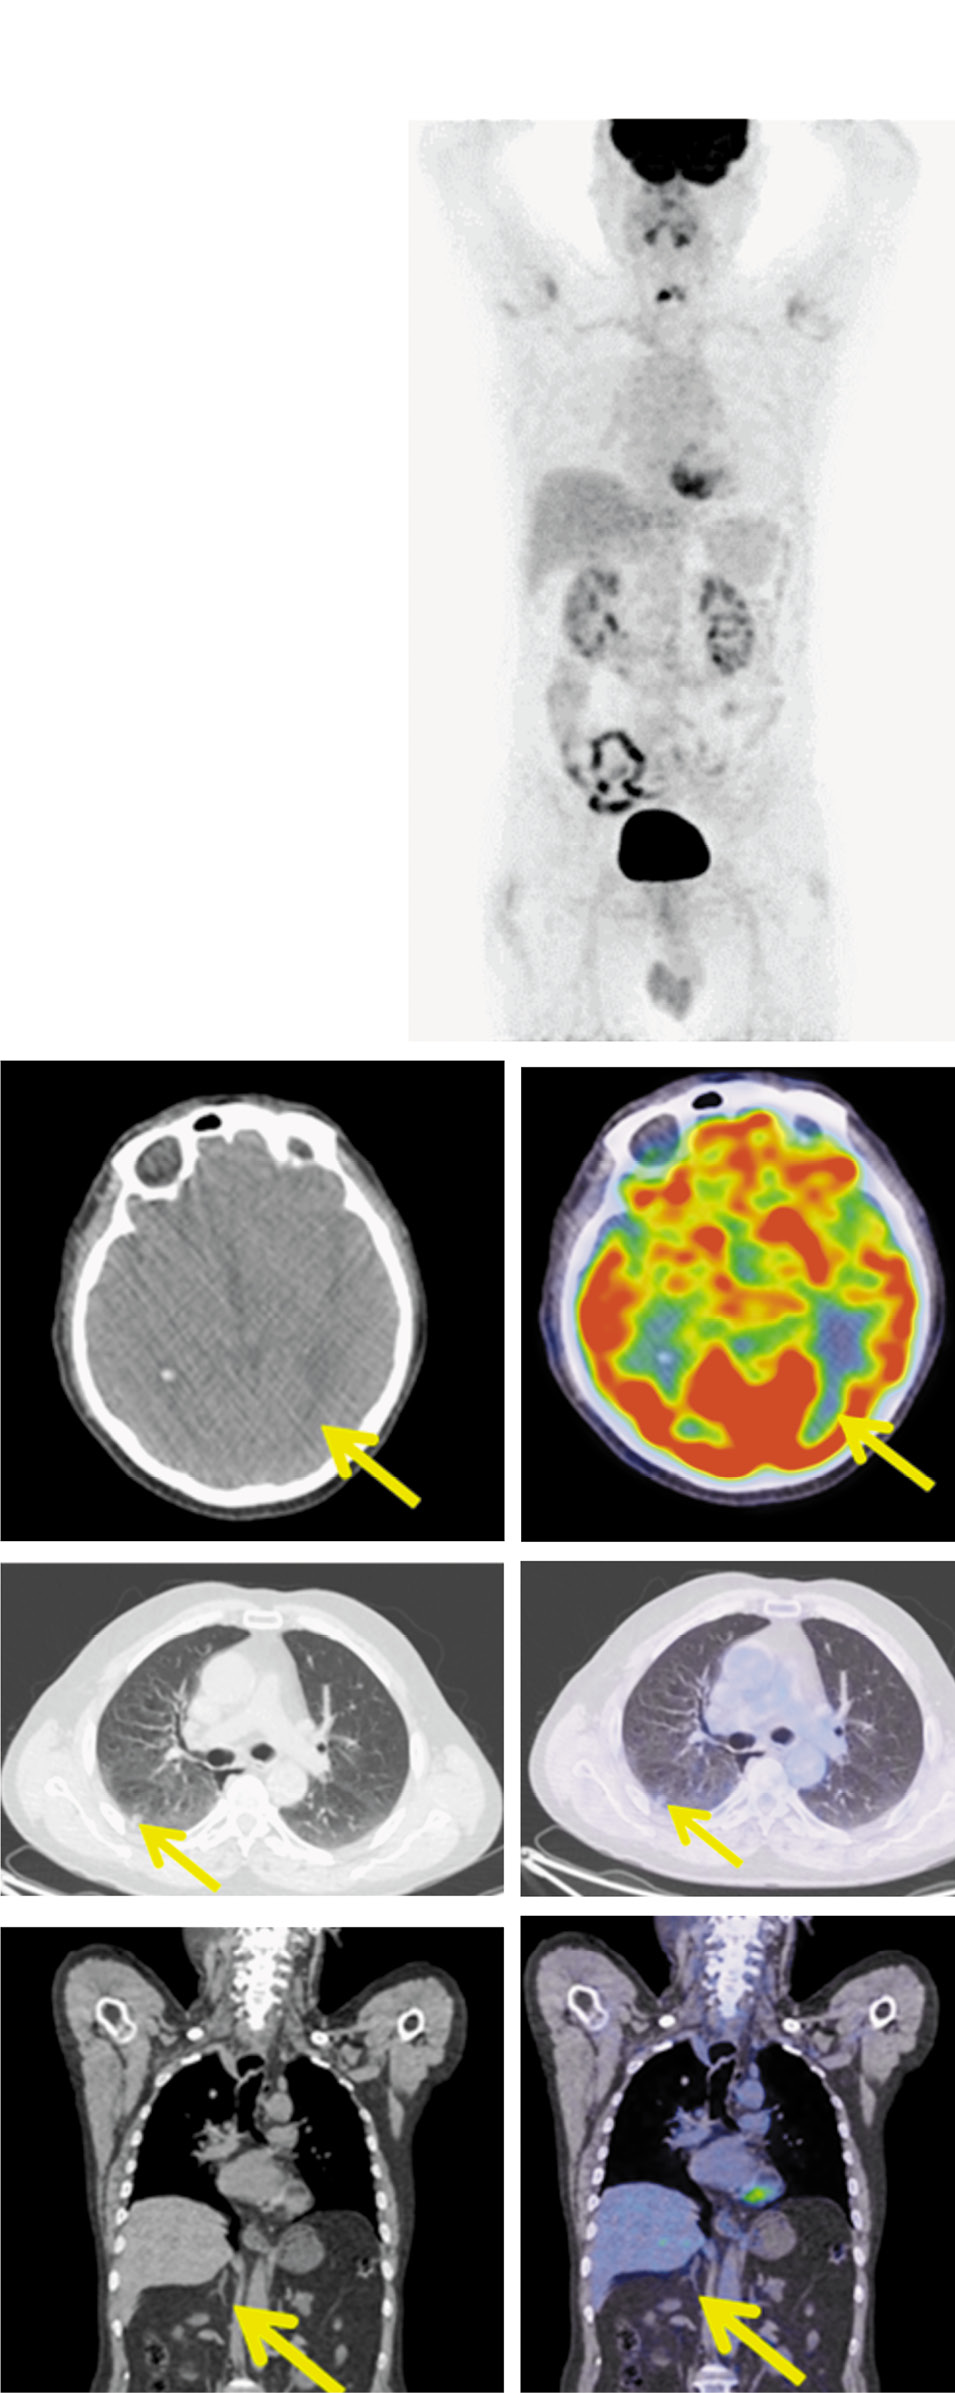

Рис. 2. Пациент Н.,64 года. До лечения. На проекциях максимальной интенсивности (MIP), аксиальных и корональных КТ и ПЭТ/КТ-проекциях в затылочной доле слева имеется аметаболический очаг размером до 17×10 мм. В субплевральном отделе S6 правого легкого определяется образование размером до 12 мм с лучистым контуром, нешироко контактирующее с костальной плеврой, с метаболической активностью ФДГ; SUVmax=2,09. В области шеи справа – увеличенные лимфатические узлы: латеральный – до 10 мм, с диффузной фиксацией РФП (SUVmax=2,14), надключичный – 15×10 мм (SUVmax=6,07). Ретротрахеально справа – инфильтрат без четких контуров, сливающийся с правой стенкой пищевода, размером до 19×41×58 мм, с повышенной активностью ФДГ (SUVmax=14,30). Увеличены лимфатические узлы: преваскулярные – до 9 мм с повышенной метаболической активностью ФДГ (SUVmax=12,80), паратрахеальные верхней группы – до 12 мм (SUVmax=9,2). В теле правого надпочечника – образование однородной плотности размером до 13×16 мм, с повышенной метаболической активностью ФДГ (SUVmax=5,08).

Fig. 2. A 64-year-old patient N. Before the treatment. MIP, axial and coronal CT and PET/CT images showing the nonmetabolic lesion measuring 17×10 mm in the left occipital lobe. The lesion measuring 12 mm with cord-like boundaries and slightly contacting with the costal pleura, with FDG uptake (SUVmax=2,09) is detected in the subpleural section of the right lung S6 segment. There are the enlarged lymph nodes in the right cervical region: lateral lymph nodes measuring 10 mm, with diffuse RFP uptake (SUVmax=2.14), the supraclavicular lymph nodes measuring 15×10 mm (SUVmax=6.07). In the right paratracheal space is an infiltrate with poorly defined boundaries, merging with the right esophageal wall, measuring 19×41×58 mm, without increased RFP uptake (SUVmax=14.30). The lymph nodes are enlarged: the prevascular lymph nodes measuring 9 mm with increased FDG uptake (SUVmax=12.80), the upper paratracheal lymph nodes group measuring 12 mm (SUVmax=9.2). The lesion of a homogeneous density in the right adrenal gland, measuring 13×16 mm, with increased RFP uptake (SUVmax=5.08) is detected.

Для оценки распространенности опухолевого процесса 21.02.2019 выполнена комбинированная позитронно-эмиссионная и рентгеновская КТ (ПЭТ-КТ) с 18-фтордезоксиглюкозой. В субплевральном отделе S6 правого легкого определяется опухоль размером до 12 мм с лучистым контуром, контактирующая с костальной плеврой, с метаболической активностью 18F-фтордезоксиглюкозы (ФДГ), SUVmax=2,09.

В области шеи справа определяются лимфатические узлы: латеральный – до 10 мм, с диффузной фиксацией радиофармпрепарата (SUVmax=2,14); надключичный – 15×10 мм (SUVmax=6,07).

Ретротрахеально справа имеется инфильтрат без четких контуров, сливающийся с правой стенкой пищевода, размером до 19×41×58 мм, с повышенной активностью ФДГ SUVmax=14,30. Обнаружены увеличенные лимфатические узлы: преваскулярные – до 9 мм с повышенной метаболической активностью ФДГ (SUVmax=12,80); паратрахеальные верхней группы – до 12 мм (SUVmax=9,20).

В теле правого надпочечника определяется образование однородной плотности размером до 13×16 мм с повышенной метаболической активностью ФДГ (SUVmax=5,08; рис. 2).